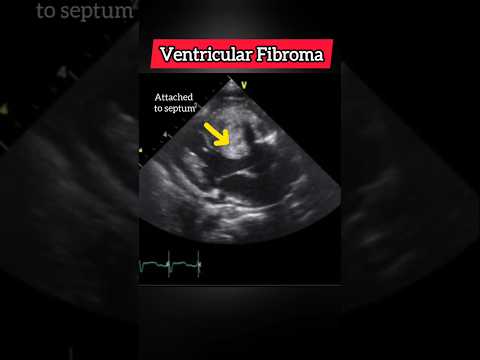

Fibroma: Typically solitary, very bright echogenic mass with shadowing due to calcification, well-circumscribed, often larger, does not regress, commonly in LV free wall or septum.

To confirm LV fibroma vs rhabdomyoma, the key modality is Cardiac MRI — echo alone cannot definitively distinguish them. Here’s the clean, practical approach used clinically: